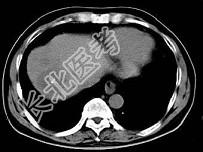

- 单项选择题根据所提供的图像,最可能的诊断是 ( )

A、肝内多发血管瘤

B、肝多发血管瘤并肝癌

C、多发肝囊肿

D、胆管细胞癌

E、以上都不是